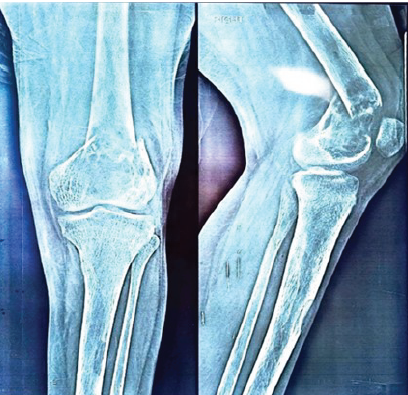

Locked Knee and Inferior Patellar Dislocation in an Elderly Patient: A Case Report and Review of the Literature